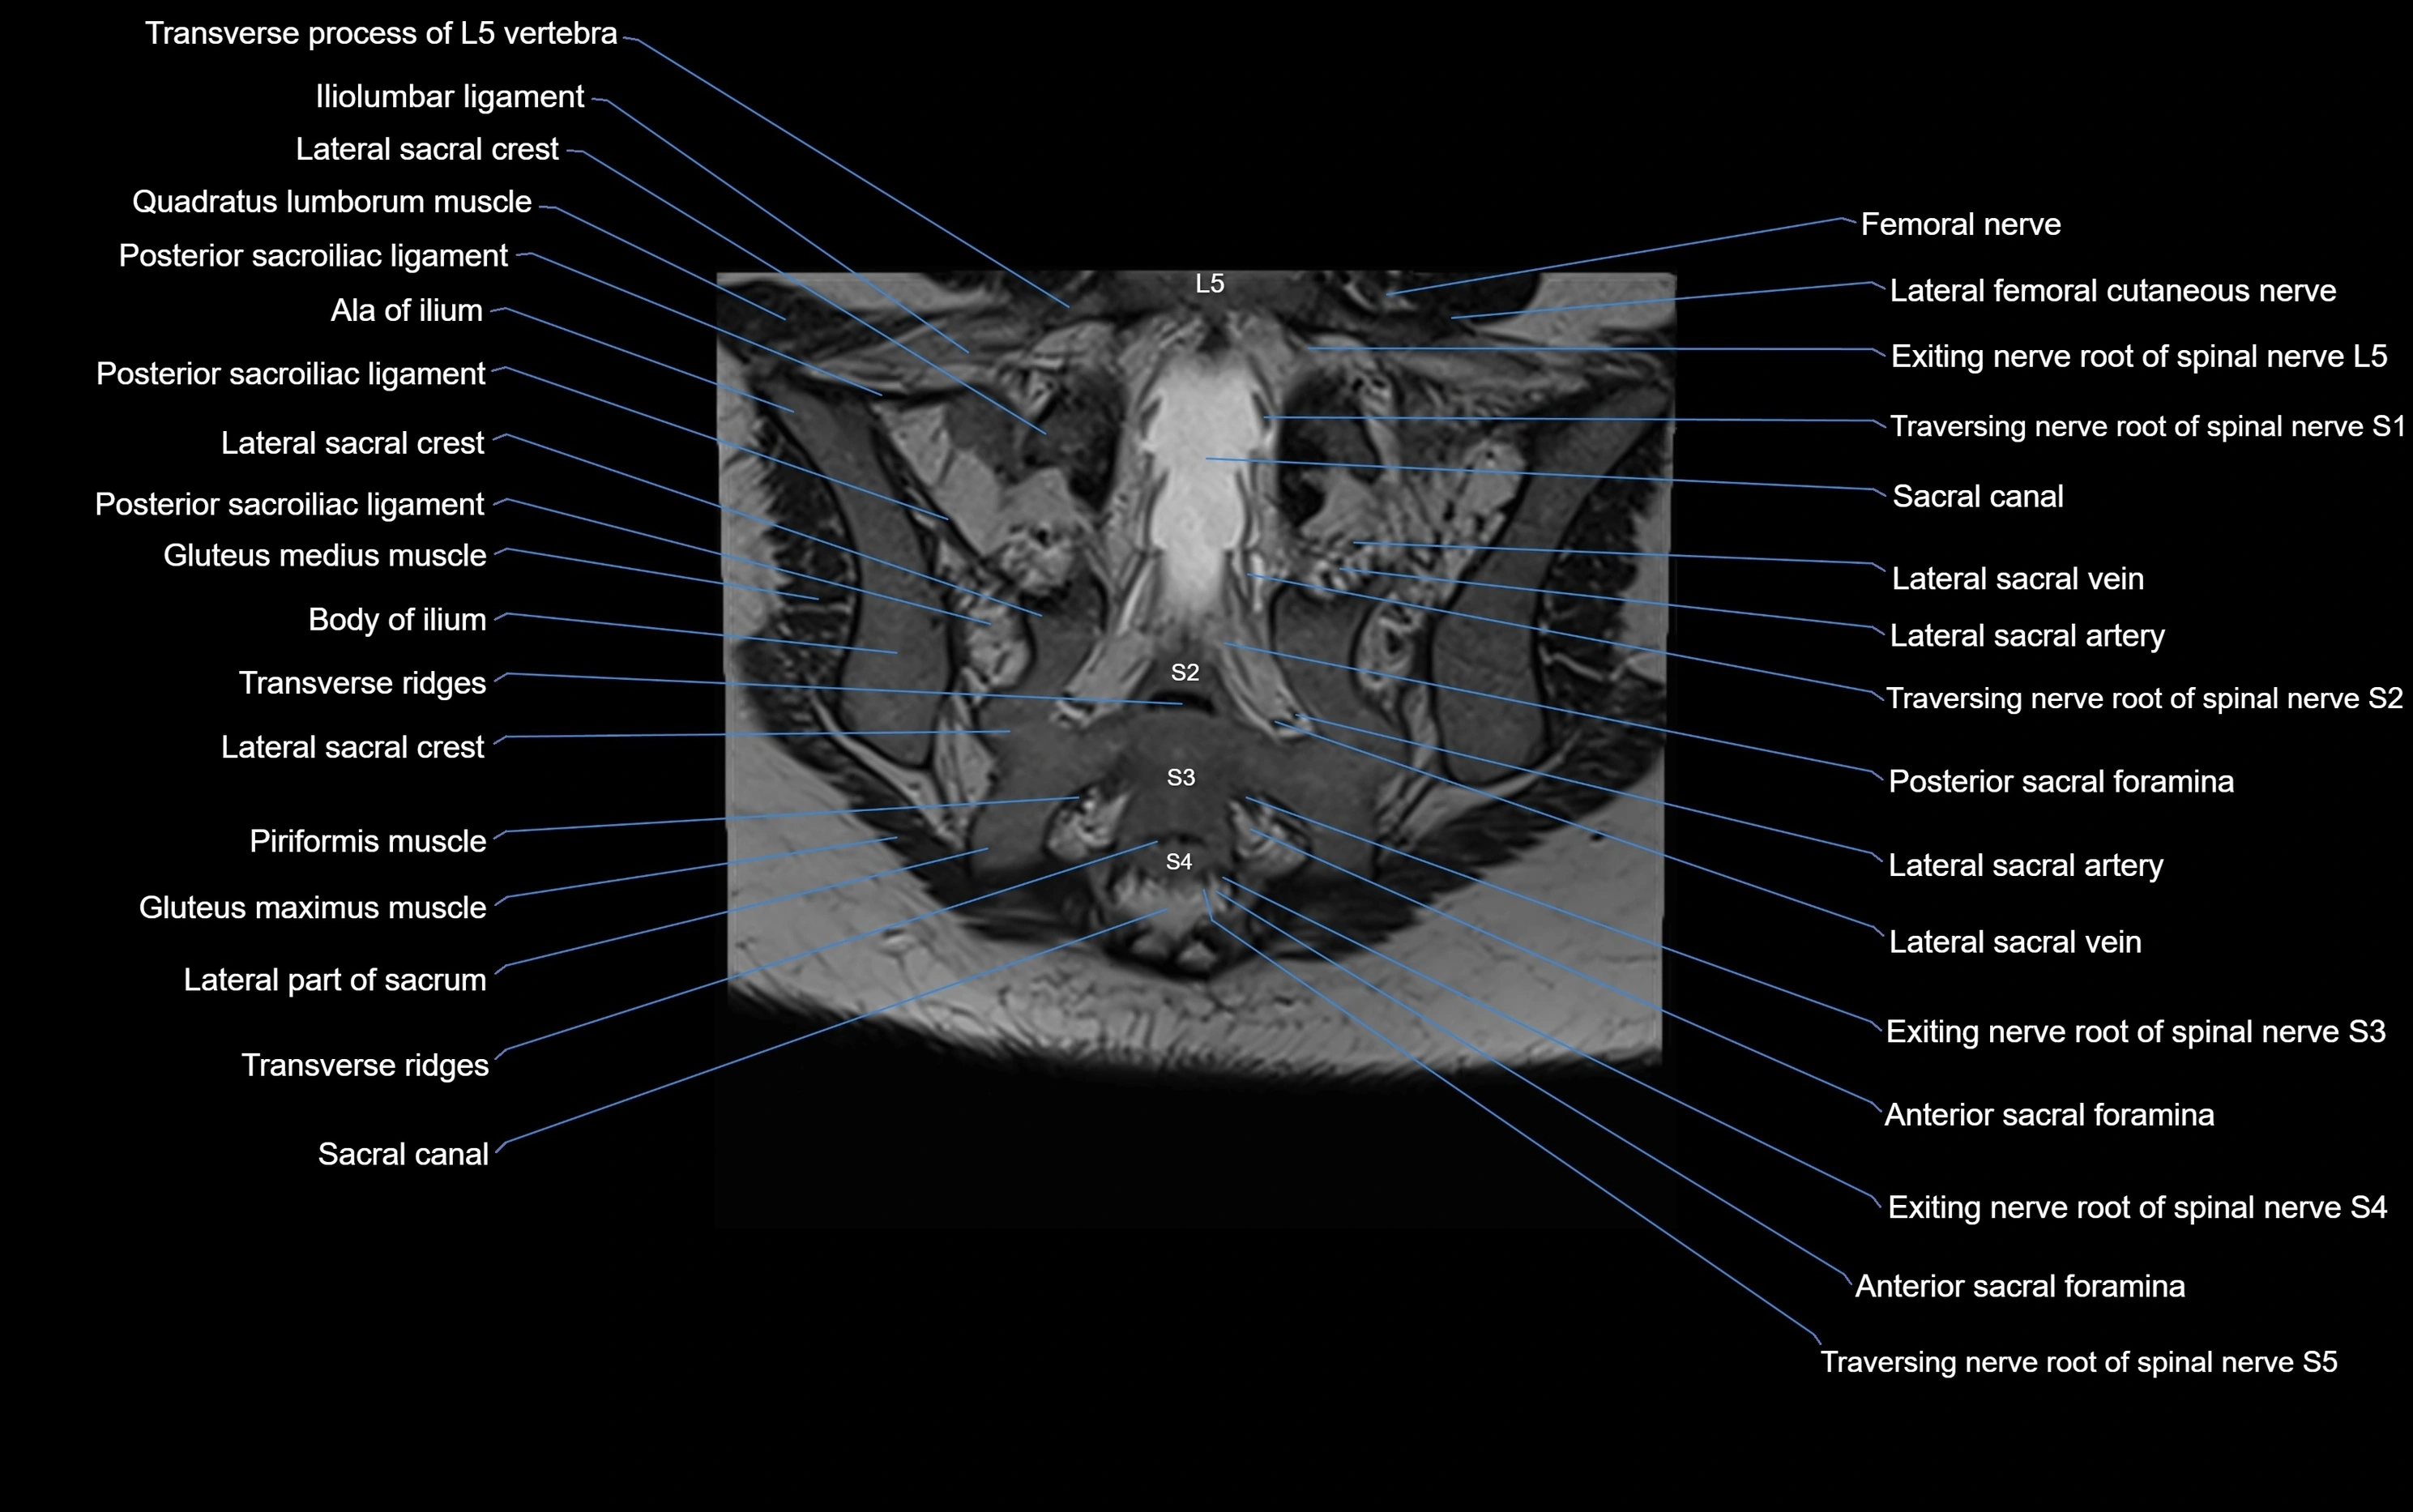

MRI image

image